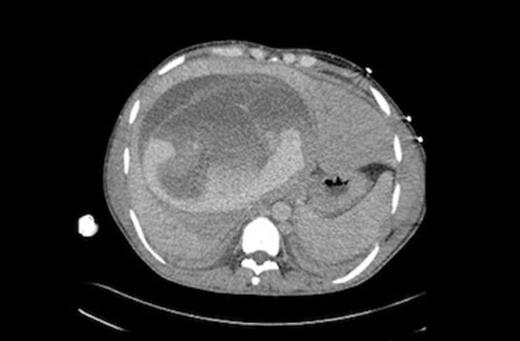

Repeat CT scan and angiography (Figures 1&2) revealed a 17cm mass occupying the right lobe of the liver with evidence of intrahepatic arterial and portal venous contrast extravasation. There was disruption of the normal right portal venous anatomy with the left portal vein being visible but displaced. Two arterial bleeding points were embolized. The underlying nature of the mass was unknown.

Indirect portography demonstrating a disruption of the intra hepatic right portal vein with extravasation of contrast into a hepatic mass.